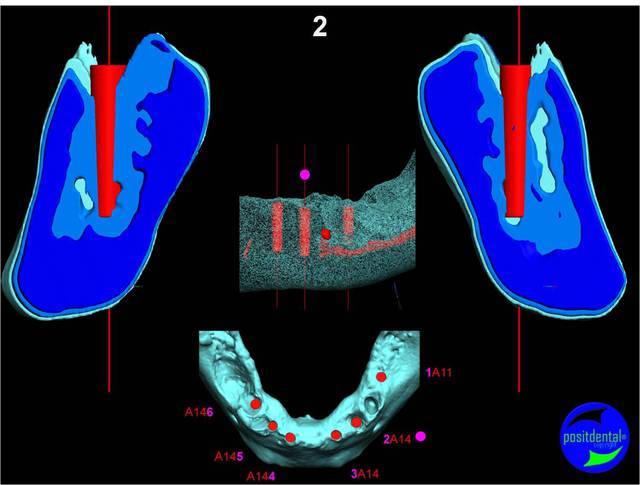

en attendant la pano voici les coupes de la S.I.A.O.

en haut en bas N° de planche